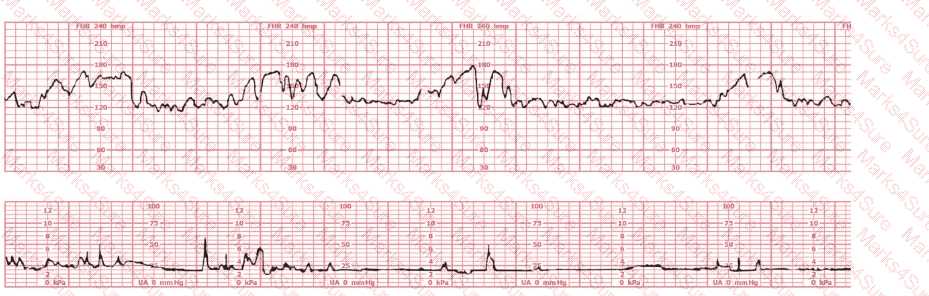

A woman has been 5 cm dilated for the past 3 hours. The tracing shown has developed over the last 30 minutes. The best initial course of action is to: